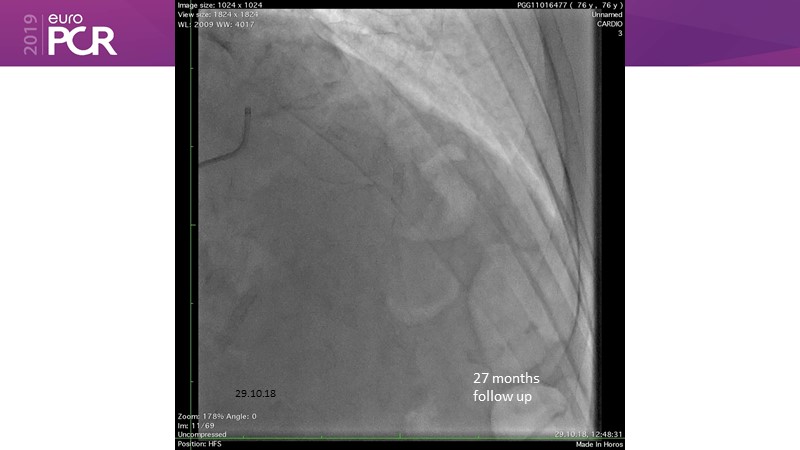

Consult this session to learn about the DCB-only concept, treatment methodology and consensus group recommendations, and discover the latest scientific evidence of DCB-only in de novo lesions and in complex PCIs.